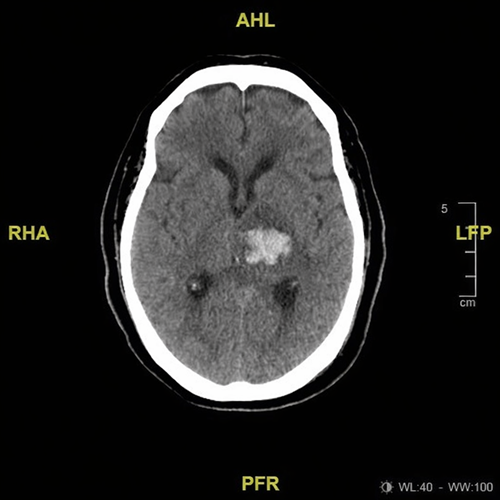

Tomografía de cráneo

- Hemorragia intraparenquimatosa talámica izquierda

- ICH score: 1 punto

- Evento vascular cerebral hemorrágico (hemorragia talámica izquierda)

Se trata de un caso clásico de hemorragia intracerebral hipertensiva, secundaria a daño crónico de arterias perforantes profundas. La localización talámica explica la combinación de alteraciones motoras y del estado de alerta.